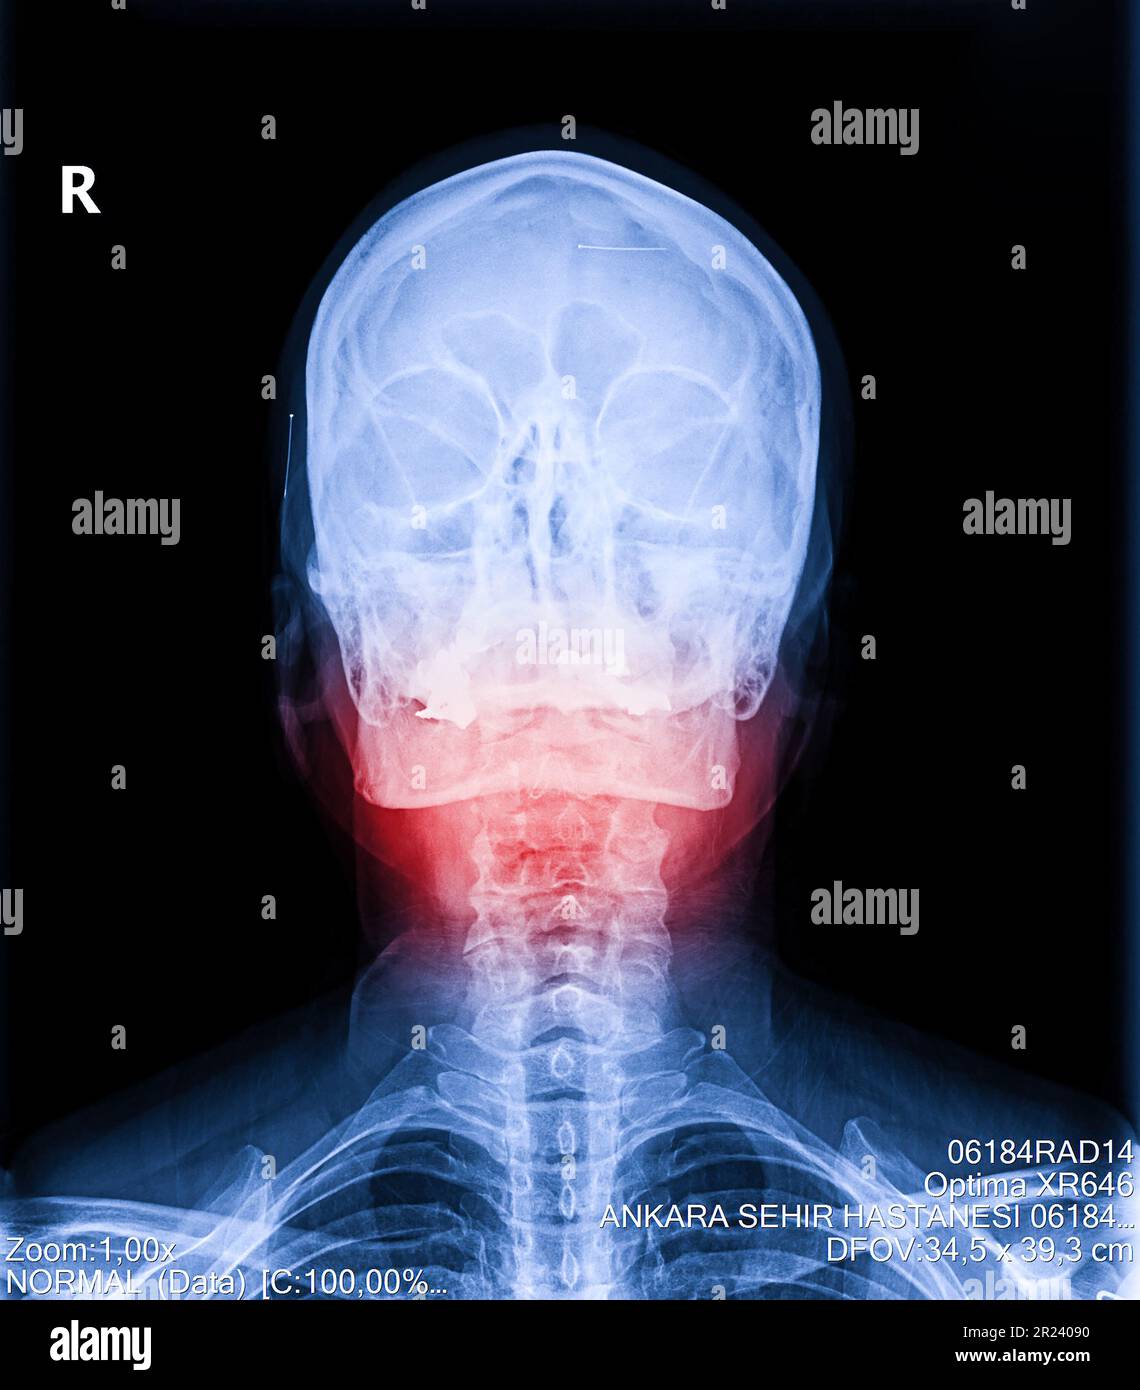

From www.alamy.com

Xray of neck and cervical spine view. Image of radiography from patient who have neck and jaw What Is Compression In The Neck spinal cord compression can occur anywhere from your neck (cervical spine) down to your lower back (very top of lumbar spine). A mass can include a tumor or bone fragment. spinal cord compression occurs when a mass places pressure on the cord. watching you walk to see if spinal compression is affecting your gait. Imaging tests can. What Is Compression In The Neck.